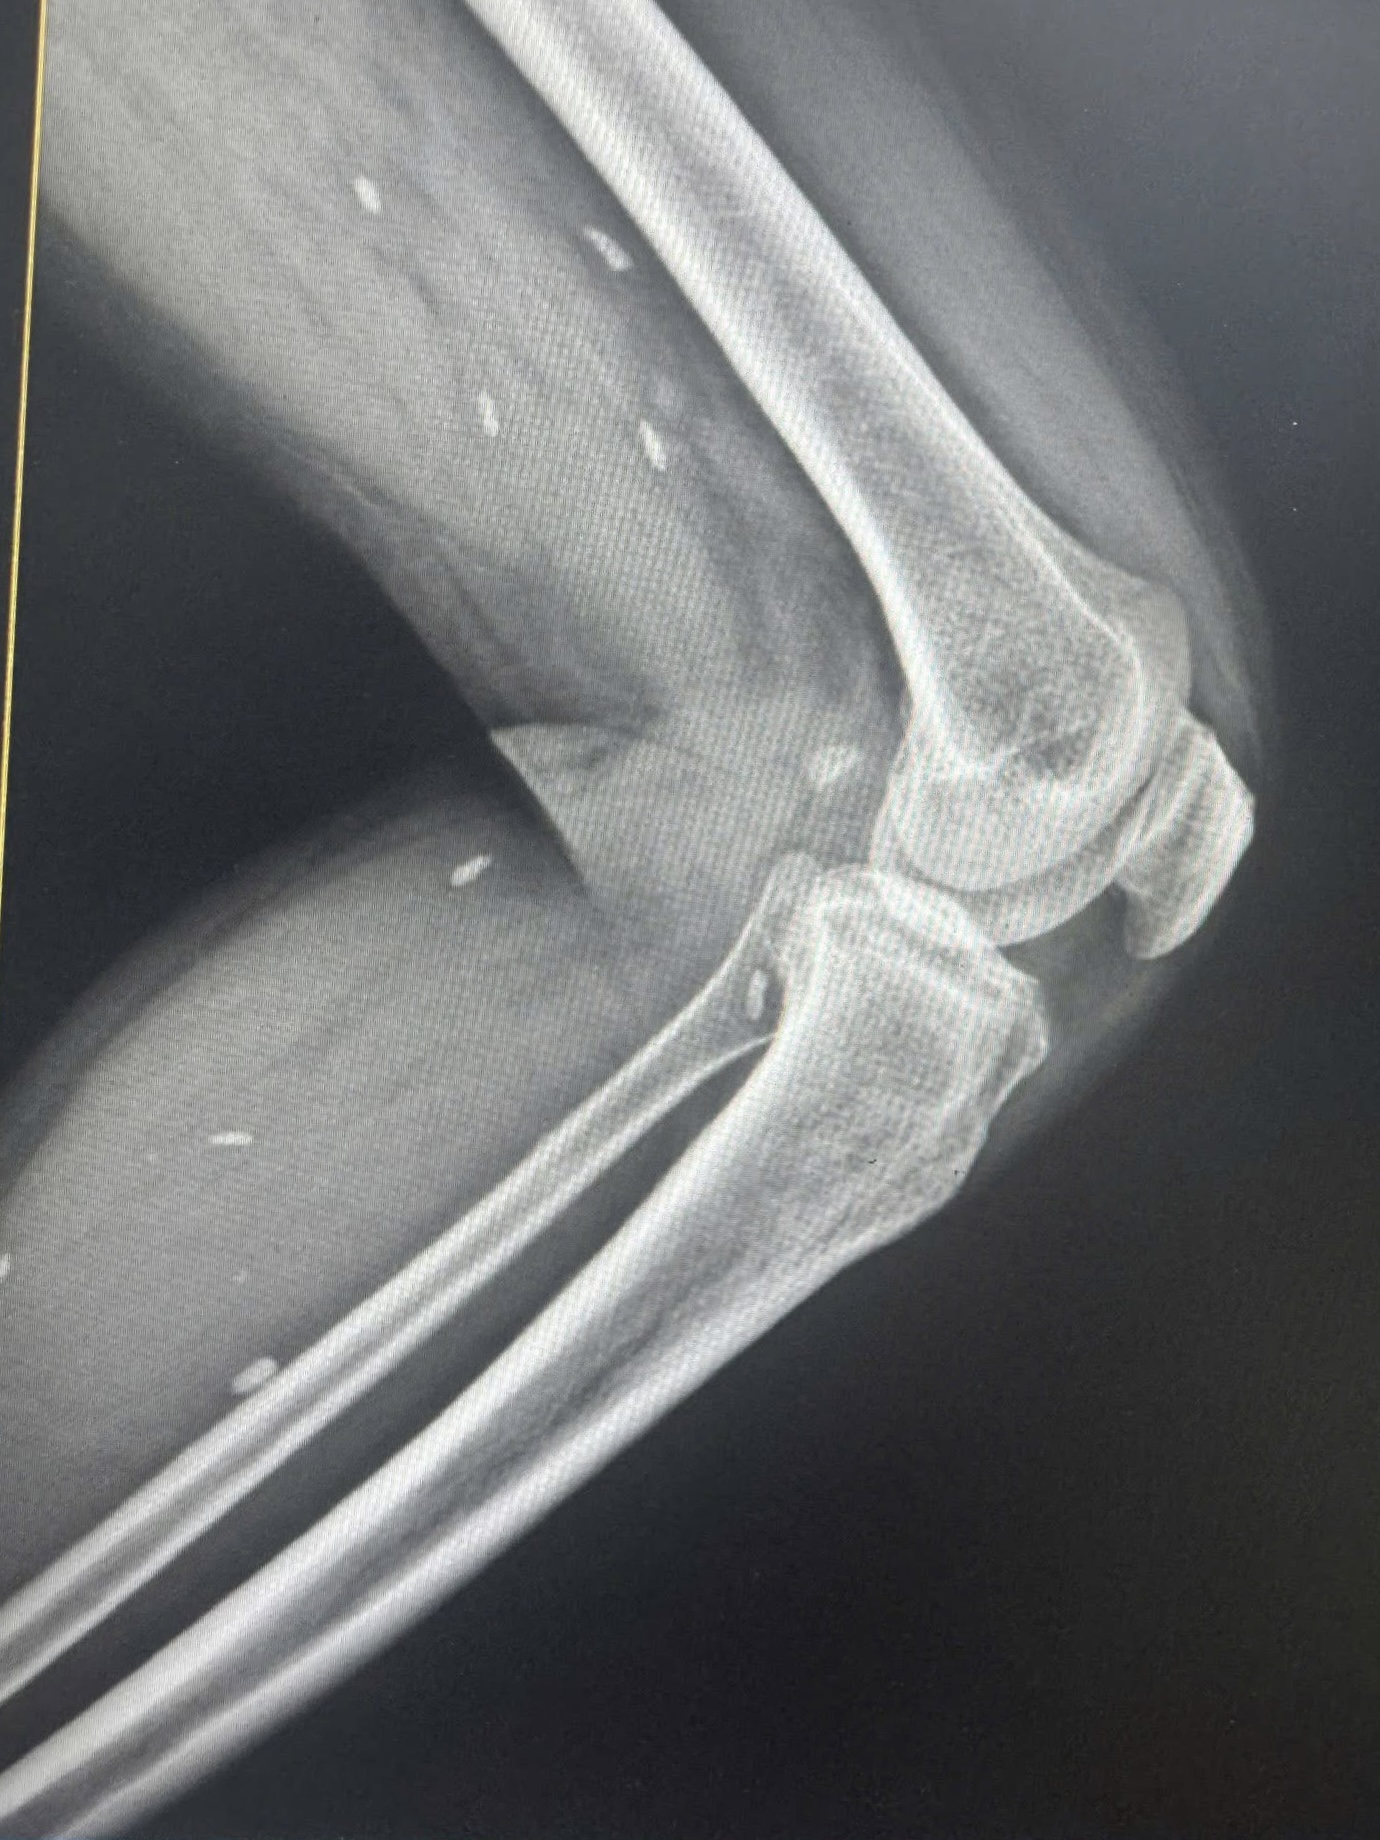

Nhiều kén sán kích thước như hạt gạo nằm rải rác ở các mô vùng xương đùi và cẳng chân bệnh nhân.

Bác sĩ Đỗ Hồng Thanh, Phó Giám đốc Trung tâm Y tế khu vực Thạch Hãn chia sẻ với Sức khỏe & Đời sống , kết quả X – quang phát hiện nhiều kén sán kích thước như hạt gạo nằm rải rác ở các mô vùng xương đùi và cẳng chân bệnh nhân.